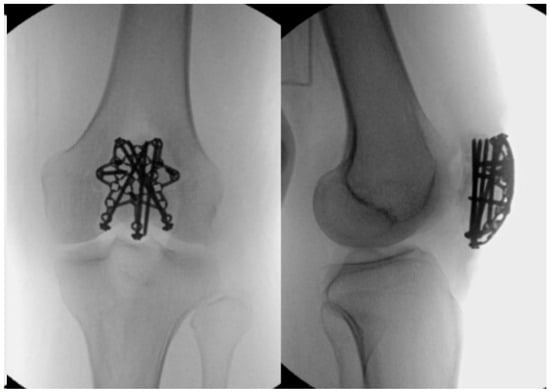

2.3. Tension Band Wire

2.4. Cannulated Screws